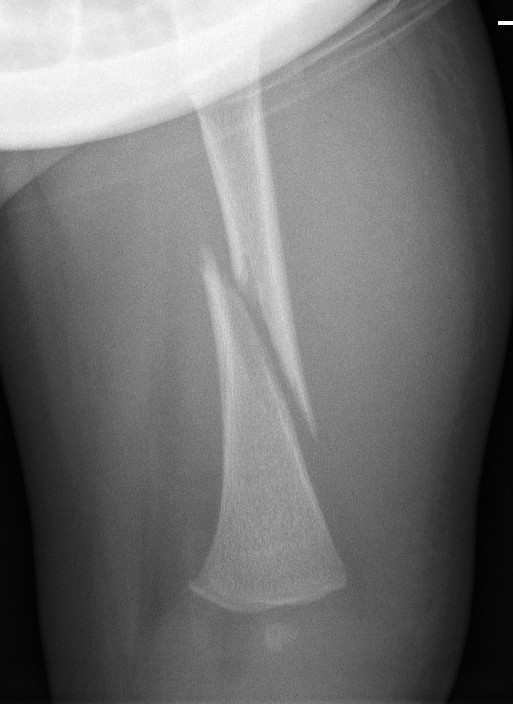

Spiral Fracture Femur X Ray . Pelvic with lateral hip radiograph. Ct or mri can be. Normal radiograph with persistent symptoms needs further ix. Spiral fractures are complete fractures of long bones that result from a rotational force applied to the bone. It occurs when a long bone is twisted with force. There is a markedly displaced spiral fracture through the shaft of the femur, with anterior angulation of. Morgan m, spiral fracture of the femur. This article explains the potential. They can also show the type of fracture. A spiral fracture is a type of bone fracture.